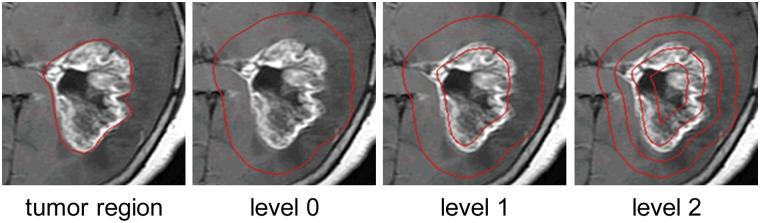

Automatic classification of tissue types of region of interest (ROI) plays an important role in computer-aided diagnosis. In the current study, we focus on the classification of three types of brain tumors (i.e., meningioma, glioma, and pituitary tumor) in T1-weighted contrast-enhanced MRI (CE-MRI) images. Spatial pyramid matching (SPM), which splits the image into increasingly fine rectangular subregions and computes histograms of local features from each subregion, exhibits excellent results for natural scene classification. However, this approach is not applicable for brain tumors, because of the great variations in tumor shape and size. In this paper, we propose a method to enhance the classification performance. First, the augmented tumor region via image dilation is used as the ROI instead of the original tumor region because tumor surrounding tissues can also offer important clues for tumor types. Second, the augmented tumor region is split into increasingly fine ring-form subregions. We evaluate the efficacy of the proposed method on a large dataset with three feature extraction methods, namely, intensity histogram, gray level co-occurrence matrix (GLCM), and bag-of-words (BoW) model. Compared with using tumor region as ROI, using augmented tumor region as ROI improves the accuracies to 82.31% from 71.39%, 84.75% from 78.18%, and 88.19% from 83.54% for intensity histogram, GLCM, and BoW model, respectively. In addition to region augmentation, ring-form partition can further improve the accuracies up to 87.54%, 89.72%, and 91.28%. These experimental results demonstrate that the proposed method is feasible and effective for the classification of brain tumors in T1-weighted CE-MRI.

感兴趣区域(ROI)的组织类型自动分类在计算机辅助诊断中起着重要作用。在当前研究中,我们专注于在T1加权对比增强磁共振成像(CE-MRI)图像中对三种脑肿瘤(即脑膜瘤、胶质瘤和垂体瘤)进行分类。空间金字塔匹配(SPM)将图像分割成越来越精细的矩形子区域,并计算每个子区域的局部特征直方图,在自然场景分类中表现出优异的结果。然而,由于肿瘤形状和大小的巨大差异,这种方法不适用于脑肿瘤。在本文中,我们提出了一种提高分类性能的方法。首先,通过图像膨胀得到的增强肿瘤区域被用作ROI,而不是原始肿瘤区域,因为肿瘤周围组织也可以为肿瘤类型提供重要线索。其次,将增强肿瘤区域分割成越来越精细的环形子区域。我们使用三种特征提取方法,即强度直方图、灰度共生矩阵(GLCM)和词袋(BoW)模型,在一个大型数据集上评估了所提方法的有效性。与使用肿瘤区域作为ROI相比,使用增强肿瘤区域作为ROI时,强度直方图、GLCM和BoW模型的准确率分别从71.39%提高到82.31%、从78.18%提高到84.75%、从83.54%提高到88.19%。除了区域增强之外,环形分割可以进一步将准确率提高到87.54%、89.72%和91.28%。这些实验结果表明,所提方法对于T1加权CE-MRI中的脑肿瘤分类是可行且有效的。